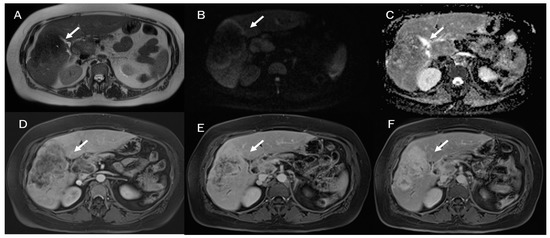

Despite the challenging nature of this task, conducting a differential diagnosis between ICC and other liver lesions, especially concerning HCC and combined hepatocellular cholangiocarcinoma (Figure 1), is mandatory to conduct appropriate treatment planning [9,10]. To help radiologists and clinicians, several authors have proposed radiomics models to better define tumor characteristics and disease progression [11,12].

Figure 1.

Combined hepatocellular cholangiocarcinoma MRI assessment: the lesion (arrow) shown in T2-W sequence (A); targetoid appearance, with restricted diffusion in b800 s/mm2 (B); and progressive contrast enhancement during contrast study (arterial phase (C) and portal phase (D)).